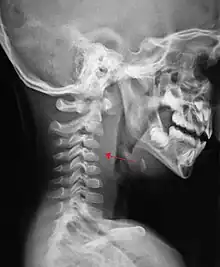

A lateral cervical spine X-ray demonstrating prevertebral soft tissue swelling (marked by the arrow) as seen in a person with a retropharyngeal abscess

X-ray of the neck often (80% of the time) shows swelling of the retropharyngeal space in affected individuals. If the retropharyngeal space is more than half of the size of the C2 vertebra, it may indicate retropharyngeal abscess.[5]